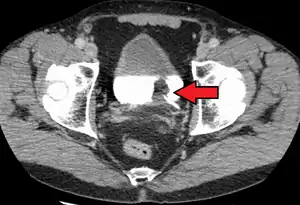

If invasive or high grade (includes carcinoma in situ) cancer is detected on TURBT, an MRI and/or CT scan of the abdomen and pelvis or urogram and CT chest should be conducted for disease staging and to look for cancer spread (metastasis).[56] Increase in alkaline phosphatase levels without evidence of liver disease should be evaluated for bone metastasis by a bone scan.[57] Although 18F-fluorodeoxyglucose (FDG)-positron emission tomography (PET)/CT has been explored as a viable method for staging, there is no consensus to support its role in routine clinical evaluations.[54]

The most common sites for bladder cancer metastases are the lymph nodes, bones, lung, liver, and peritoneum.[78] The most common sentinel lymph nodes draining bladder cancer are obturator and internal iliac lymph nodes. The location of lymphatic spread depends on the location of the tumors. Tumors on the superolateral bladder wall spread to external iliac lymph nodes. Tumors on the neck, anterior wall and fundus spread commonly to the internal iliac lymph nodes.[79] From the regional lymph nodes (i.e. obturator, internal and external lymph nodes) the cancer spreads to distant sites like the common iliac lymph nodes and paraaortic lymph nodes.[80] Skipped lymph node lesions are not seen in bladder cancer.[79]

A bilateral pelvic lymphadenectomy should accompany radical cystectomy. At minimum, a standard template of lymphadenectomy should be followed by removing the external and internal iliac and obturator lymph node.[124] When performing a lymphadenectomy, the surgeon can either remove lymph nodes from a smaller (standard) or from larger (extended) area. In comparison with a standard lymph node dissection, having an extended dissection may reduce a person's likelihood of death from any reason, including dying from bladder cancer.[125] The extended procedure may lead to more serious unwanted effects and may or may not influence the likelihood of the cancer recurring over time.[125] The rate of not-so-serious side effects may be similar for both surgeries.[125]